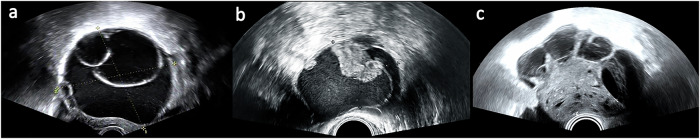

Materials and methods: This retrospective study included 916 women with ovarian tumors in southeast China who underwent surgery with clear pathology and preoperative US examination. The data set was divided into a training (80%) and a validation (20%) set. The test set consisted of 81 women with ovarian tumors from southwest and northeast China. DL models based on three backbone architectures, ResNet-50 (residual CNN), VGG16 (plain CNN), and Vision Transformer (ViT), were trained to classify benign, borderline, and malignant ovarian tumors. The diagnostic efficiency of primary US doctors combined with the DL model was compared with the ADNEX model and a US expert. Additionally, we compared the diagnostic performance of primary US doctors before and after being assisted by the integrated framework combining visual DL models and large language models.